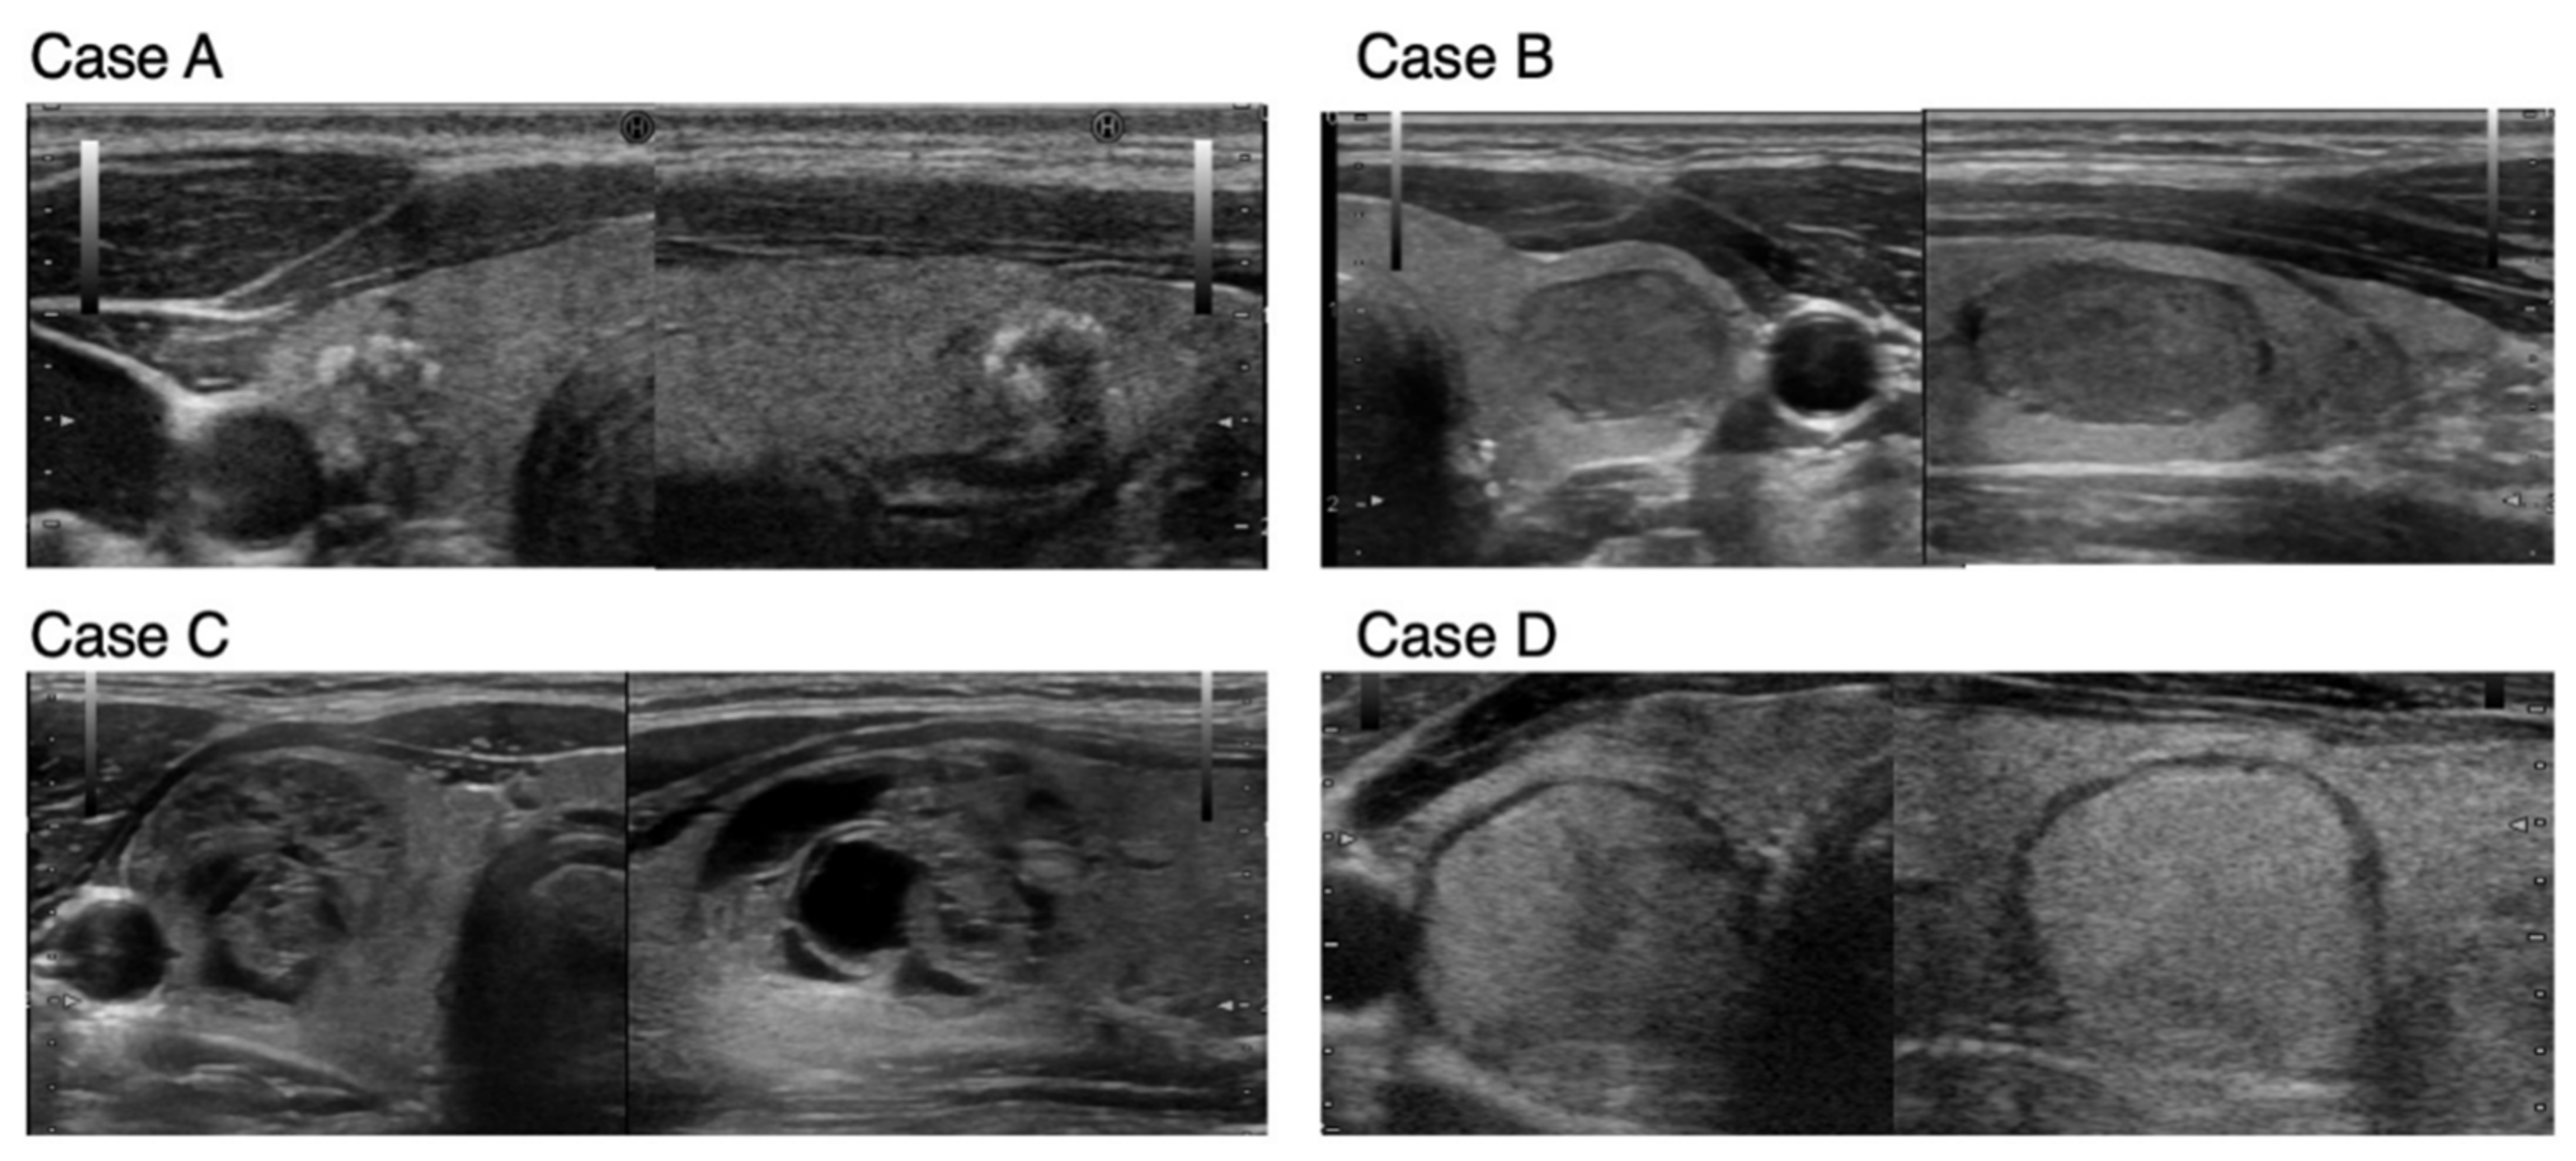

Diagnostic Strategies for Thyroid Nodules Based on

Diagnostic Strategies for Thyroid Nodules Based on